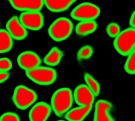

The task of nuclei segmentation can be roughly divided into two stages: the first stage is extracting the foreground(nuclei), the second stage is segmenting the connected foreground area into separated nuclei and finding out the boundary of each nucleus. Our method intends to merge these two steps by extracting the nuclei and their edges at the same time. That is the reason why it is named ”nuclei-boundary(NB) model”. As shown in Fig.3, the output of the NB model has three channels, each has the same height and width with the input image. Its values represent the probabilities of each pixel being , or class, respectively. The manual annotation for our segmentation problem is the boundary of each nucleus. A pixel belonging to the class means that it is on or inside an annotated boundary and within 2 pixel from the boundary. Pixels of the class are those that are inside annotated boundary but are not pixels. Correspondingly, the output can be regarded as an RGB image and the estimated maps of the , and are represented by red, green and blue, respectively, as shown in Fig.3. To generate the ternary mask for training, we apply a morphology operator to each nucleus to obtain the pixels, and then subtract pixels from the nucleus to get pixels.

Figure 6 shows how our method segments the nuclei step by step. The color variety is well controlled by the color normalization procedure. The prediction result shows clear nuclear areas and nucleus boundaries. In the final segmentation result and ground truth image, each nucleus is represented by a different color.

An alternative way to detect nuclei and their boundaries is training two binary classifiers to detect and the boundary separately and then merge the detections together. We apply the same method with our NB model to train the nucleus model and boundary model except that the three-class classification is replaced by binary classification. Fig. 12 depicts why the NB model outperforms the mixed nucleus model + boundary model. The NB model is able to learn the latent relationships between , and . That is, there should be no gaps between and class and should not cross the class. From the samples shown in Fig. 12, we can easily find out that NB model predicts the class and class more precisely.